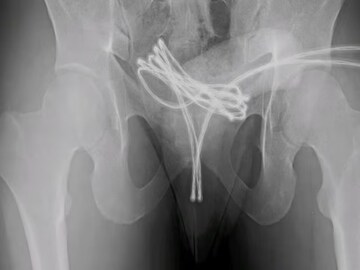

आपत्कालीन शस्त्रक्रियेनंतर तो बरा झाला, पण डॉक्टरांनी इशारा दिला आहे की, असे करणे जीवघेणे ठरू शकते. नुकताच, या प्रकरणाशी संबंधित एक अभ्यास 2020 मध्ये अमेरिकेत प्रकाशित झालेल्या एका मासिकात प्रसिद्ध झाला. नाव न सांगितलेल्या 21 वर्षीय मुलाने 'साउंडिंग' नावाचा प्रयोग केला होता. ही अशी कृती आहे ज्यात लोक गुप्तांगाच्या मूत्रमार्गात (लघवीची नळी) पातळ वस्तू टाकतात. मुलाने यूएसबी केबलला 'यू' आकाराचे वाकवून, दोन्ही टोके बाहेर ठेवून मूत्रमार्गात टाकले. पण यावेळी केबल इतकी आत गेली की तो ती काढू शकला नाही. घाबरून तो रुग्णालयात पोहोचला.

अखेर डाॅक्टरांनी बाहेर काढली केबल

जेव्हा डॉक्टरांनी तपासणी केली, तेव्हा आढळले की केबल मूत्राशयात पोहोचली होती आणि तिथेच अडकली होती. 'क्युरियस' जर्नलमध्ये प्रकाशित झालेल्या अहवालानुसार, डॉक्टरांनी आधी हाताने केबल काढण्याचा प्रयत्न केला, पण ते यशस्वी झाले नाहीत. शेवटी, मुलाला बेशुद्ध करून विशेष उपकरणांच्या मदतीने केबल काढण्यात आली. डॉक्टरांनी हळू हळू केबल बाहेर ओढली, नंतर ती कात्रीने कापली आणि दोन्ही भाग सहज बाहेर काढले.